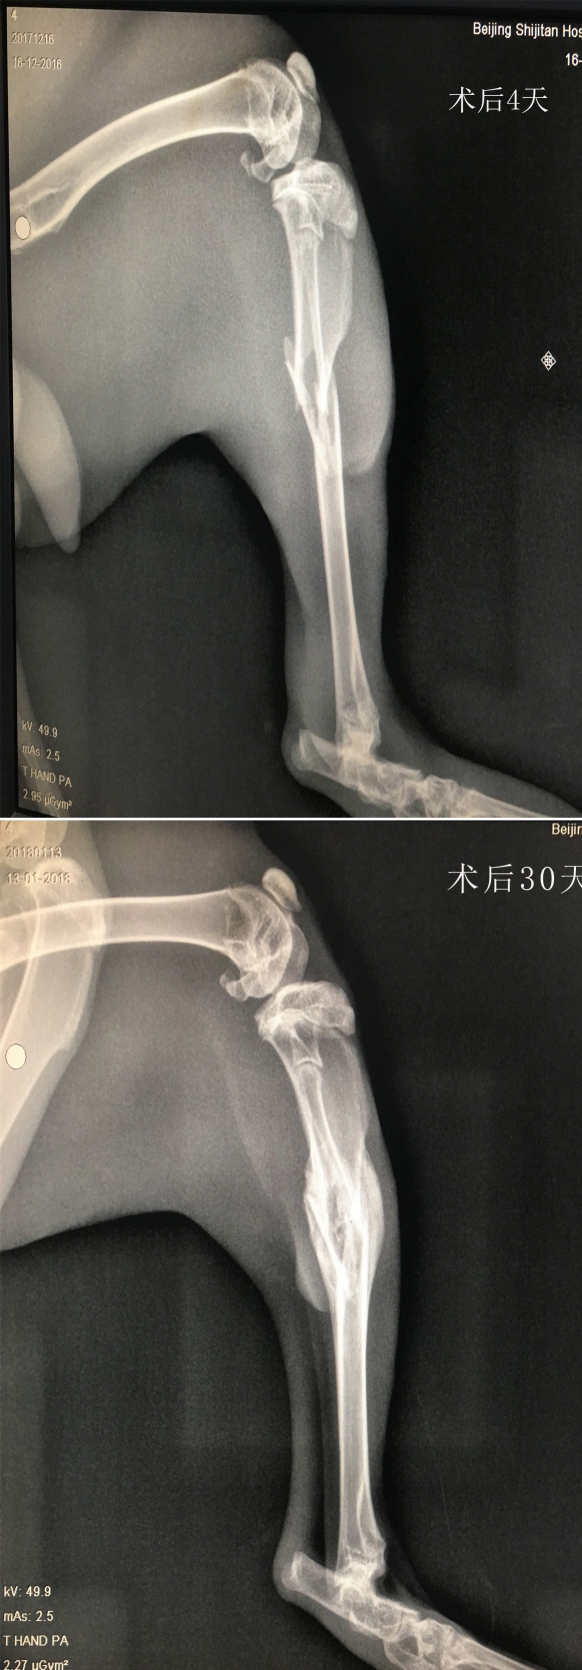

X光

2.肿瘤动物模型:在肿瘤动物模型实验中,X光技术可以与药物联用,用于肿瘤药物和治疗方法的开发、研究与评估,以及放疗的机制和方法研究。